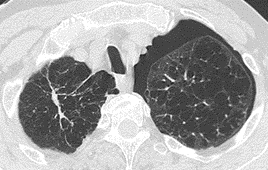

(4) 만성 폐쇄성 폐질환 (COPD)

COPD는 주로 흡연으로 인해 발병하며, 기도의 지속적인 염증과 협착으로 인해 호흡곤란이 발생합니다. 지속적인 기침과 가래가 특징적입니다.